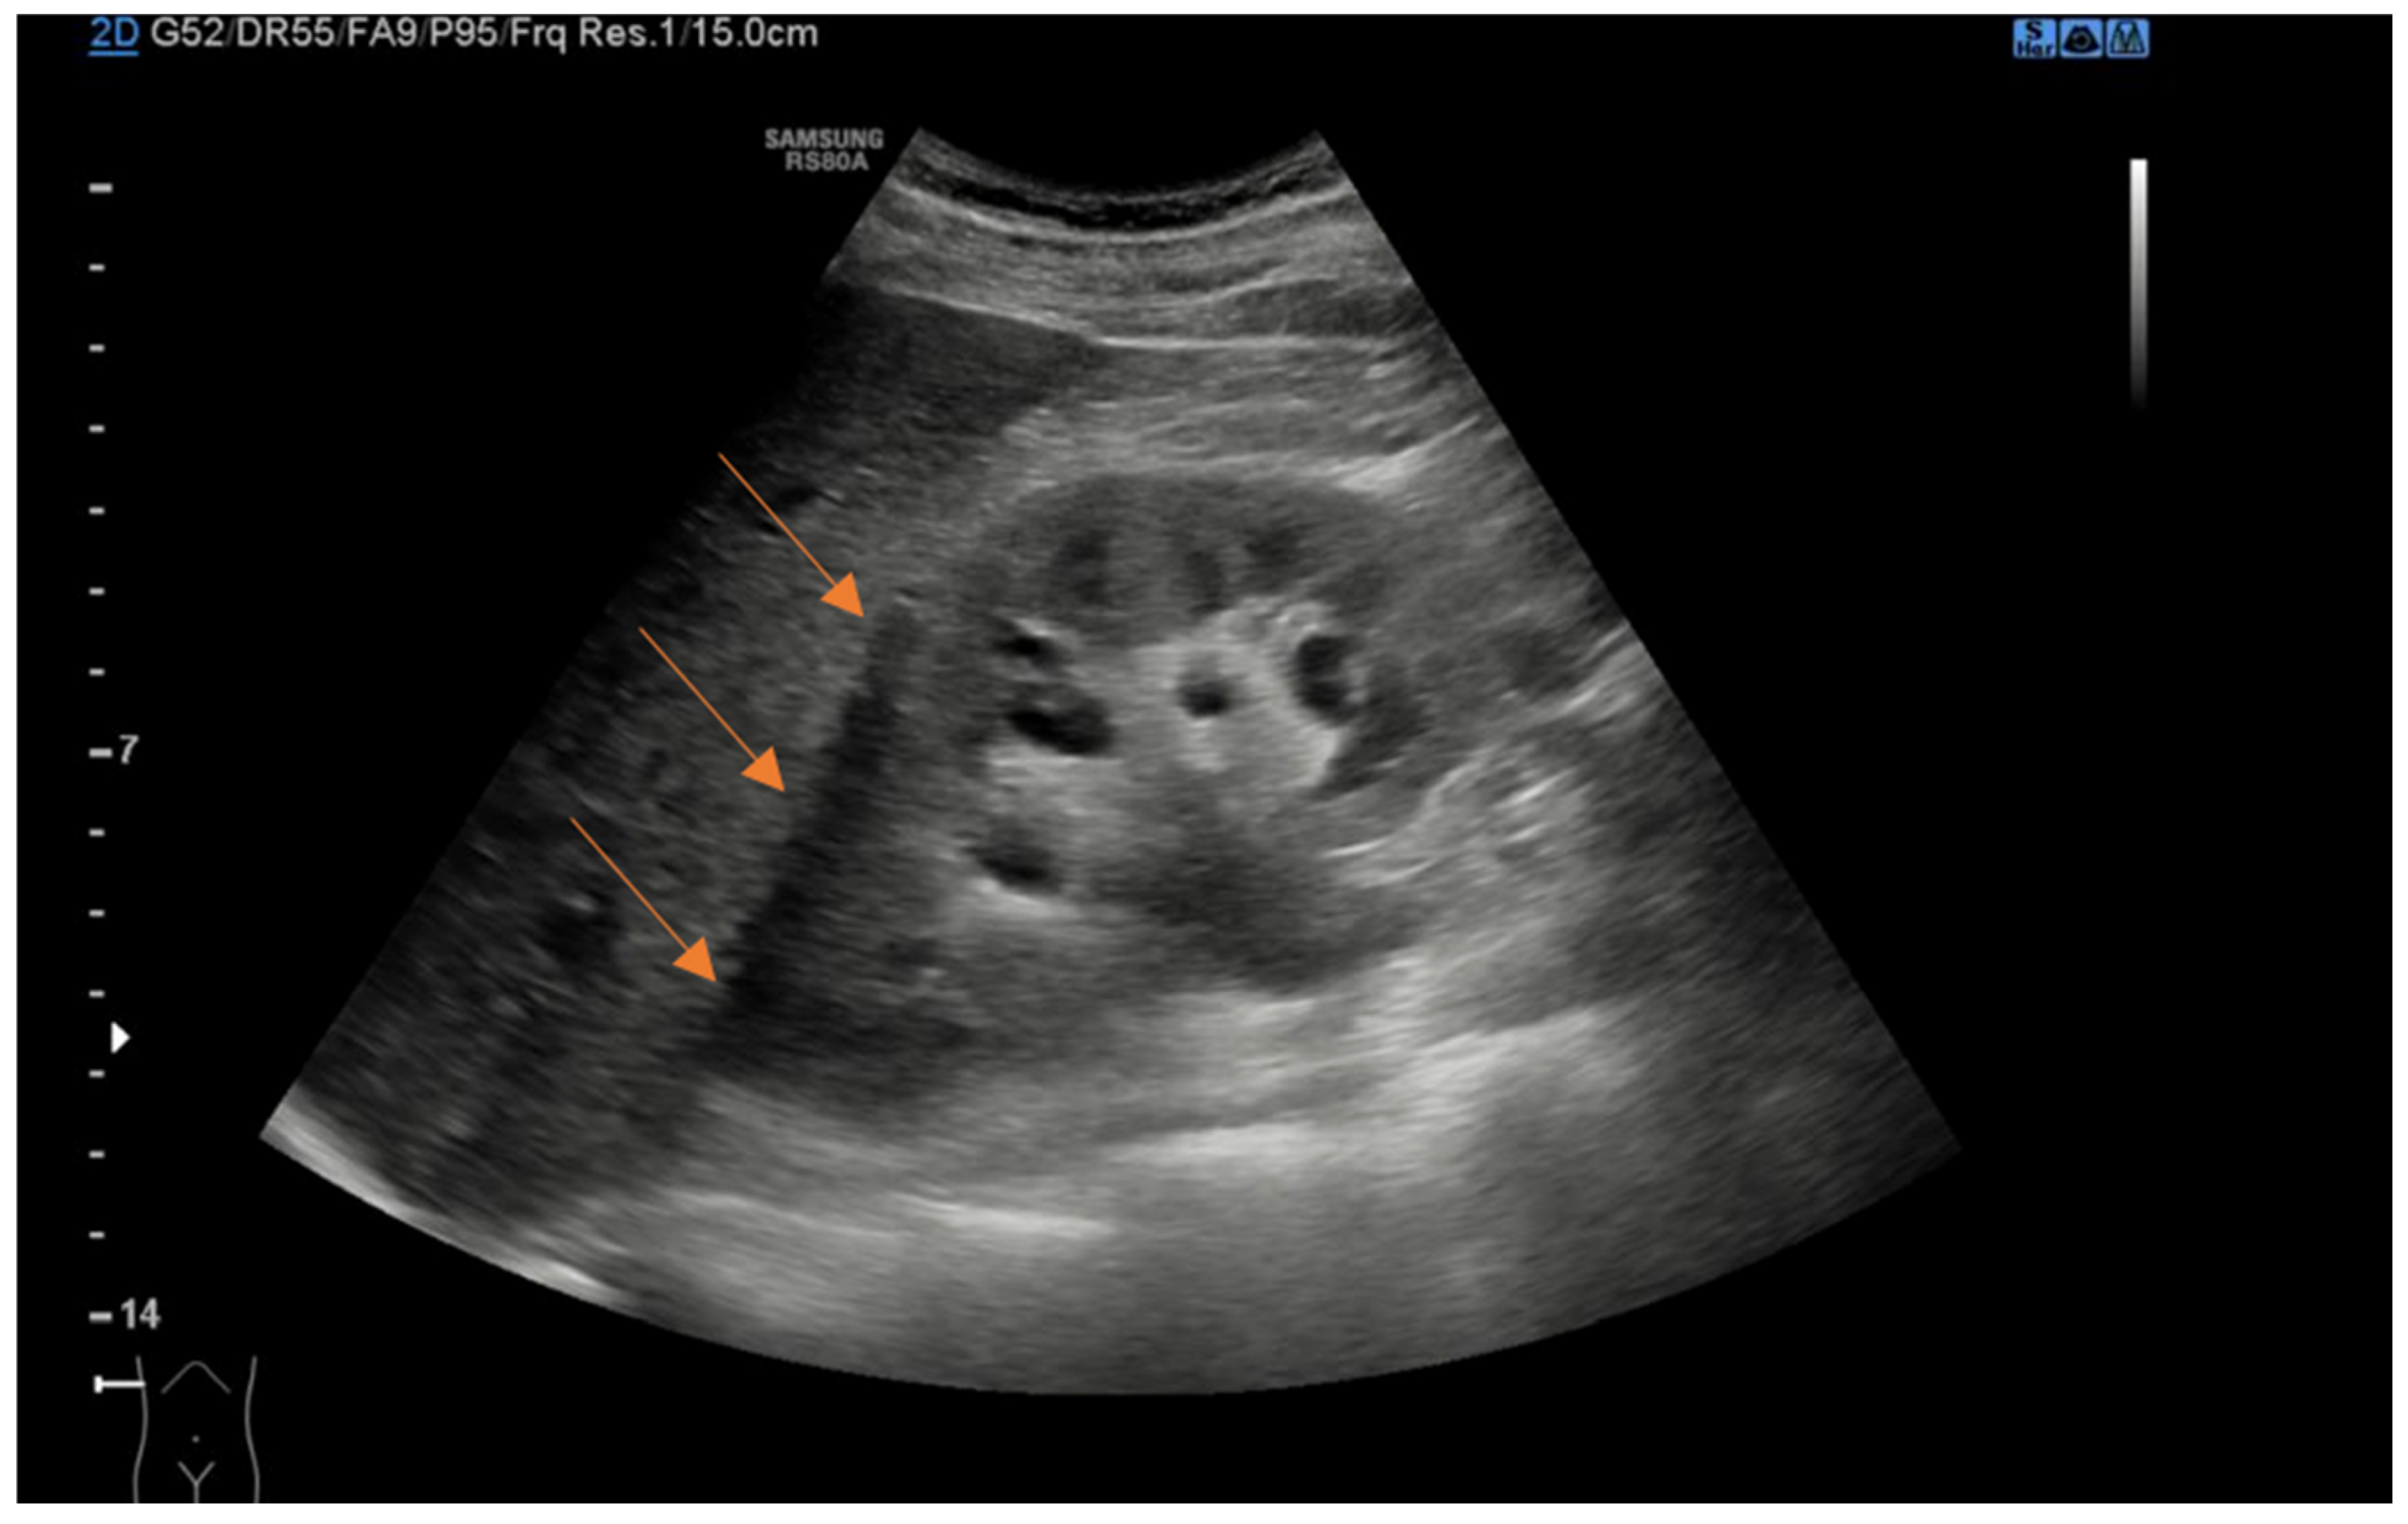

- Tsao, T.-F.; Liang, K.-W.; Huang, H.-H.; Tyan, Y.-S.; Chao, Y.-H. Sonography of Perinephric Fluid Collections: A Pictorial Essay. J. Clin. Ultrasound JCU 2019, 47, 150–160. [Google Scholar] [CrossRef]